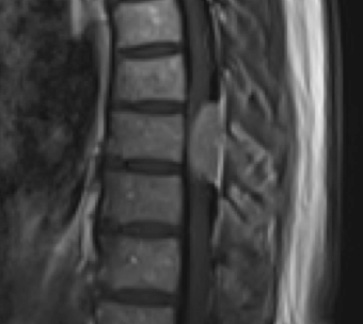

Postoperative MRI T1w demonstrating interval resection with cord re-expansion (blue arrow)

Postoperative MRI T1w demonstrating a gross total resection